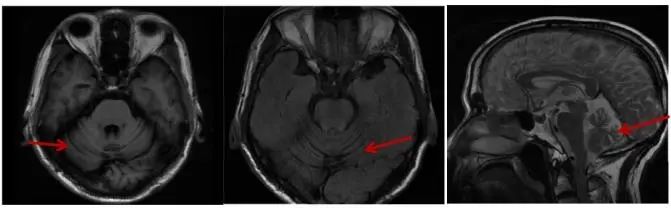

1.1 先证者 男,61岁,因“言语含糊伴行走不稳3年余”入院,主要表现为3年前出现言语含糊伴行走不稳、左足外侧麻木,无饮水呛咳、吞咽困难等,当时脊髓小脑性共济失调评估与评级量表(scale for the assessment and rating of ataxia,SARA)评分3.5分,未予特殊治疗,随后上述症状进行性加重,伴头晕、晨起下肢趾背及手掌尺侧麻木,偶有饮水呛咳,睡眠欠佳。既往有双膝关节疼痛病史。查体阳性体征:言语含糊,双眼右视时水平眼震,双侧指鼻试验欠稳准、右侧为甚,双侧跟膝胫试验欠稳准、右侧为甚,闭目难立征欠稳,步距宽,行走不稳,双侧弓形足、右侧为甚,四肢腱反射活跃,右侧双划征可疑阳性,SARA评分12分。辅助检查:3年前入院时诱发电位、肌电图未见异常,四肢周围神经电图:左L5、S1或其周围支神经损害,头颅MRI:脑白质轻度脱髓鞘改变,小脑萎缩(图1)。此次入院诱发电位、肌电图、神经电图、皮肤交感反应、脑电图、痴呆量表等均无明显异常,头颅MRI见小脑明显萎缩,基因测序:CACNA1A CAG重复次数为 22 次(图2),在全突变范围内。诊断为脊髓小脑性共济失调 6型。

Fig.1 MRI T1, T2and sagittal maps of patient, 2023

图1 患者 2023年头颅MRI T1、T2及矢状位图 见小脑明显萎缩